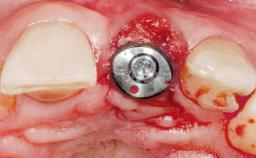

A 30-year-old female patient was referred to the office for the treatment of tooth 11. Her chief concern at the initial visit was to inquire, “Why is my tooth pink?” Upon clinical examination, it was determined that tooth 11 had a previous history of trauma and that the clinical crown had become noticeably pink in color as a result of internal resorption. This diagnosis was confirmed radiographically, indicating a large radiolucency involving the central and distal portions of the clinical crown. It was determined that restoration of this tooth was not possible, and that extraction was indicated. The presence of a mid-line diastema, which the patient wanted to reproduce, directed the treatment plan for tooth replacement utilizing a dental implant.

Placement Protocol Immediate implant placement

Tooth Site Maxillary incisor or canine

Socket Morphology Single-root socket

Socket Integrity Sufficient, with intact bone walls

Bone Volume Sufficient, with intact walls